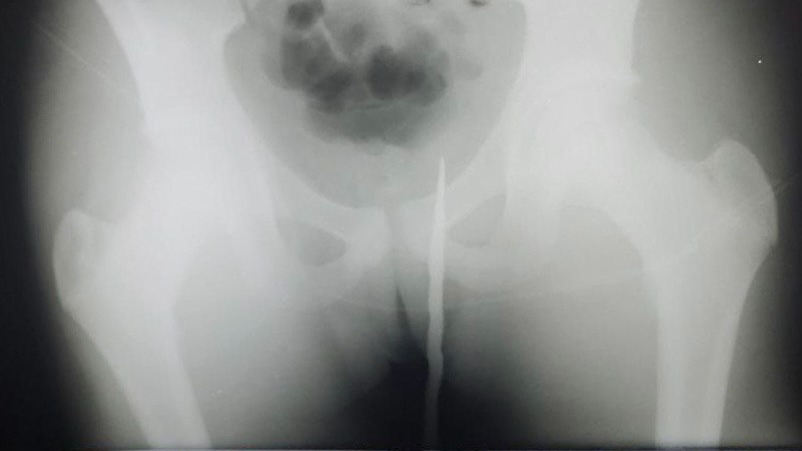

В Подмосковье подросток нечаянно напоролся на штык старинной винтовки и попал в больницу. Об этом сообщили в пресс-службе Министерства здравоохранения Московской области в пятницу, 19 мая.

Инцидент произошел в Наро-Фоминске. Во время прогулки с друзьями в лесу 14-летний подросток напоролся на старинный ржавый штык от винтовки, который вошел в мягкие ткани юноши более чем на 15 сантиметров. Пострадавшего госпитализировали.

— Из-за риска повреждения внутренних органов, прямой кишки, мочевого пузыря, вмешательство проводилось под общей анестезией, — рассказал заместитель главного врача по медицинской части, детский врач-хирург Денис Монахов.

Операция прошла успешно. Подростка оставили в отделении детской хирургии, откуда он был выписан в удовлетворительном состоянии через непродолжительное время.